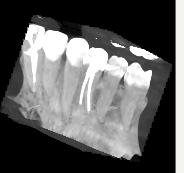

В начале июня возникла боль только при жевании нежесткой пищи в области 24 зуба. 12 июня после проведения предварительного холодового тестирования (реакции практически не было) была снята старая пломба, удален нерв, положено лекарство в каналы и поставлена временная пломба. Через 7 дней боль при жевании сохранялась, я старалась, чтобы пища не попадала на эту область. Боли в покое не было. Я говорила врачу, что болит при жевании по-прежнему, она начала пломбировать каналы и установила постоянную пломбу. Боль никуда так и не делась при жевании. 2 июля сделала КТ. 9 июля врач распломбировала 1 канал, положила туда лекарство, попросила с ней связаться через пару дней и обсудить самочувствие. Боль такая же при жевании, в покое тоже иногда что-то чувствуется. Болевой порог низкий, но не могу назвать ощущение в покое именно болью. Врач говорит о возможной трещине в зубе, вероятно она и дает боль при жевании, рекомендует диагностику на микроскопе, потому что трещины не всегда видны на КТ. Врач уточняет локализацию боли и подозревает, что болит, возможно, 25 зуб. Я кусаю ватную палочку перед зеркалом: при надкусывании палочки под 25 и 24 зубом боли нет, когда палочка находится под 23 и между 23 и 24 боль есть. Скажите, пожалуйста, может ли воспаление или иные проблемы в 24 зубе отдавать в 23?